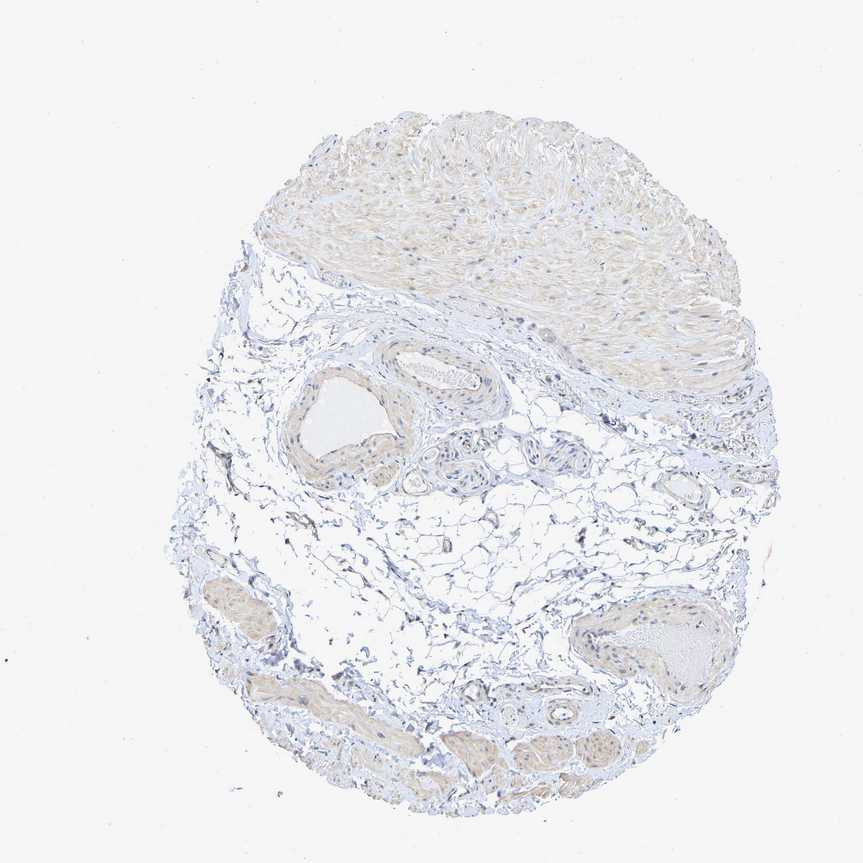

ADIPOSE TISSUE - Antibody stainingi

Antibody staining in the annotated cell types in the current human tissue is reported as not detected, low, medium, or high, based on conventional immunohistochemistry profiling in selected tissues. This score is based on the combination of the staining intensity and fraction of stained cells.

Each image is clickable and will lead to virtual microscopy that enables deeper exploration of all samples and also displays staining intensity scores, fraction scores and subcellular localization as well as patient and tissue information for each sample.

Antibody HPA019049Antibody HPA019051

Adipocytes Not detectedNot detected